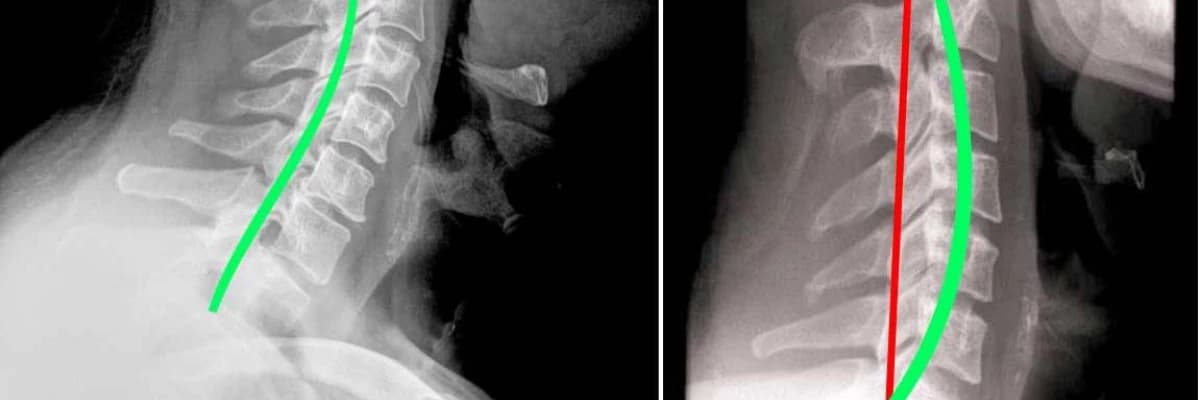

Boyun düzleşmesi; şekli ters C’ye benzeyen omurganın (resimdeki soldaki şekil) çeşitli nedenlerden dolayı I şeklini (resimdeki sağdaki şekil) almasıdır. Genelde boyun kaslarındaki spazm ve gerginlik sonrası oluşan bir durumdur. Uygun yastık kullanmama, uzun süre mobil telefon benzeri teknolojik aletler kullanma ve uzun süreler bilgisayara ekranına bakarak çalışma sonrası gelişir.